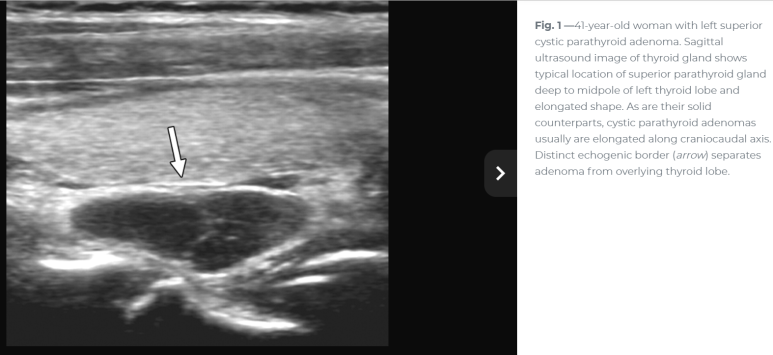

이번 사례와 같은 위치에 비슷한 모습

For nonfunctional parathyroid cysts, which are usually large simple epithelial cysts, the sonographic features are unlikely to add much specificity to the diagnosis. The primary role of ultrasound in these cases is to guide cyst aspiration for PTH assay to confirm parathyroid origin and potentially for therapeutic intervention. 비기능성 낭종일 경우 초음파의 주된 역할은 부갑상선 기원을 확인하기 위해 PTH assay를 위해 낭종 흡인을 보하는 것이다.

Ultrasonography is considered to be the first line imaging modality as part of the diagnostic workup. The sensitivity and specificity of this is operator-dependent but is likely to reveal a cystic nodule that can often be difficult to differentiate from a thyroid cyst 크기가 크면? 갑상선 낭종과 구별이 어려울때도. The absence of comet tail artefacts, which, if present, would indicate a colloid cyst, as well as the lack of other cystic lesions within the thyroid lobes may raise the suspicion of a parathyroid origin. However, differentiation of parathyroid cysts from thyroid cysts based on radiological findings is challenging.